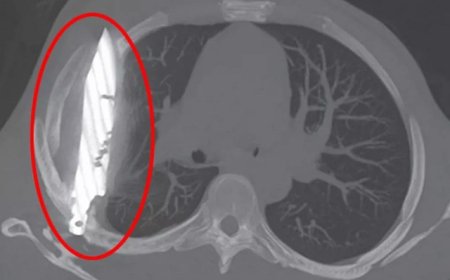

"Adətən bunun səbəbi turşu reflüksü və ya qastroezofageal reflüks xəstəliyi (GERX) olur. GERX zamanı mədədədki qalıqlar qida borusuna atılır, çünki aşağı qida borusu sfinkteri (normal halda qalıqları yalnız mədəyə "buraxan" bağlayıcı mexanizm) zəifləyir".